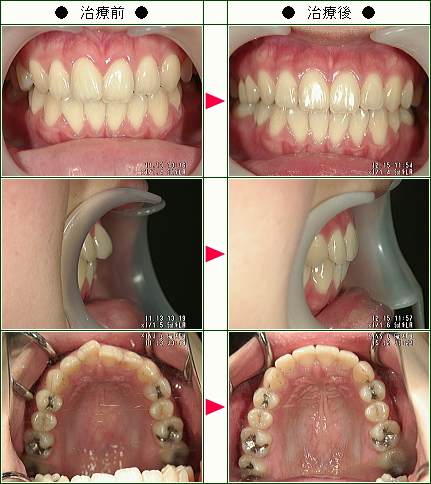

☆歯のデコボコ矯正症例(M・K様 26歳 女性)